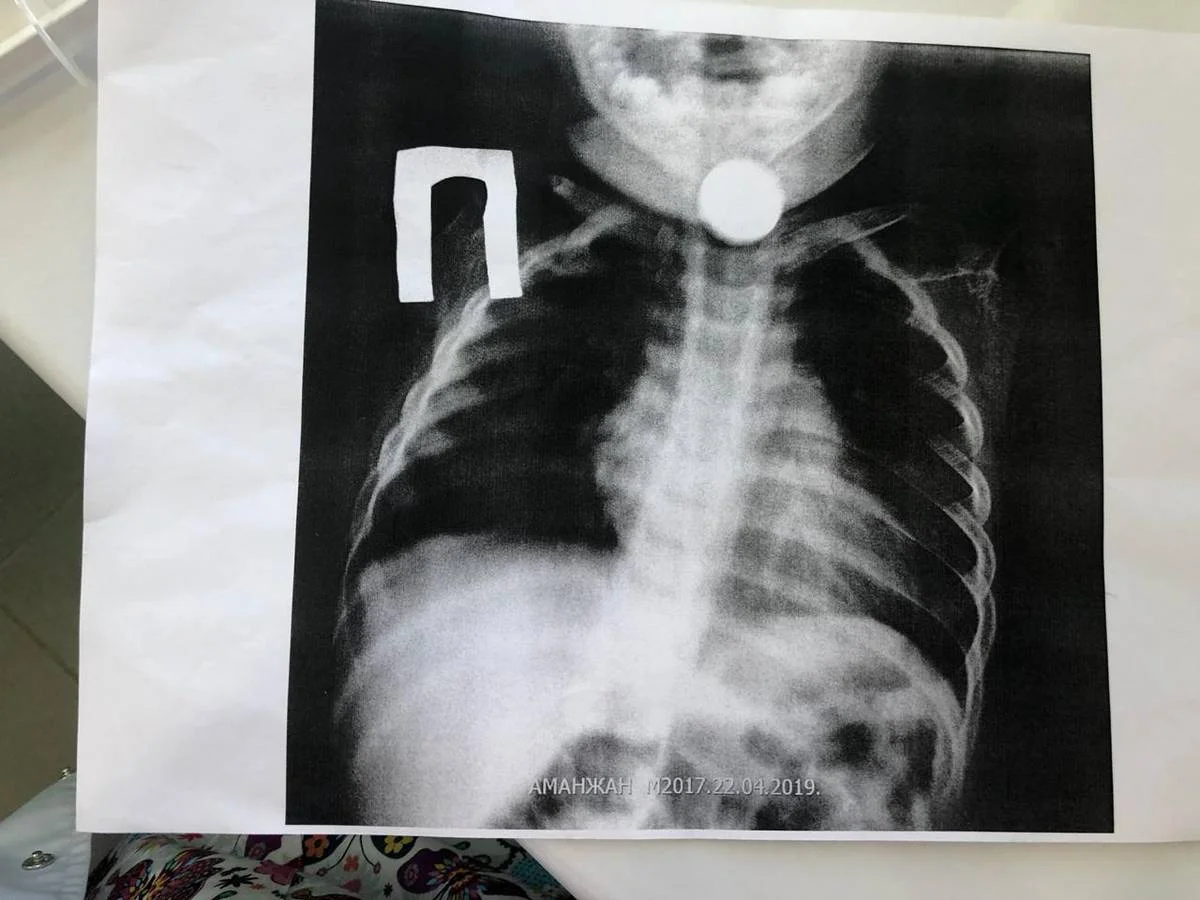

Фото предоставлено в управлении здравоохранения Мангистауской области

Инцидент произошел 22 апреля. Ребенок поступил в приемный покой областной детской больницы с жалобами на кашель и затрудненное дыхание.

Дежурный врач Насухан Отаргазиев, сделав рентген, обнаружил инородный предмет в пищеводе ребенка.

- Врач вытащил из пищевода монету номиналом в 10 тенге, используя «Катетер Фолея». Ту же методику, ранее использовал директор центральной районной больницы Бейнеу. На данный момент малыш чувствует себя хорошо, - сообщили в управлении здравоохранения Мангистауской области.